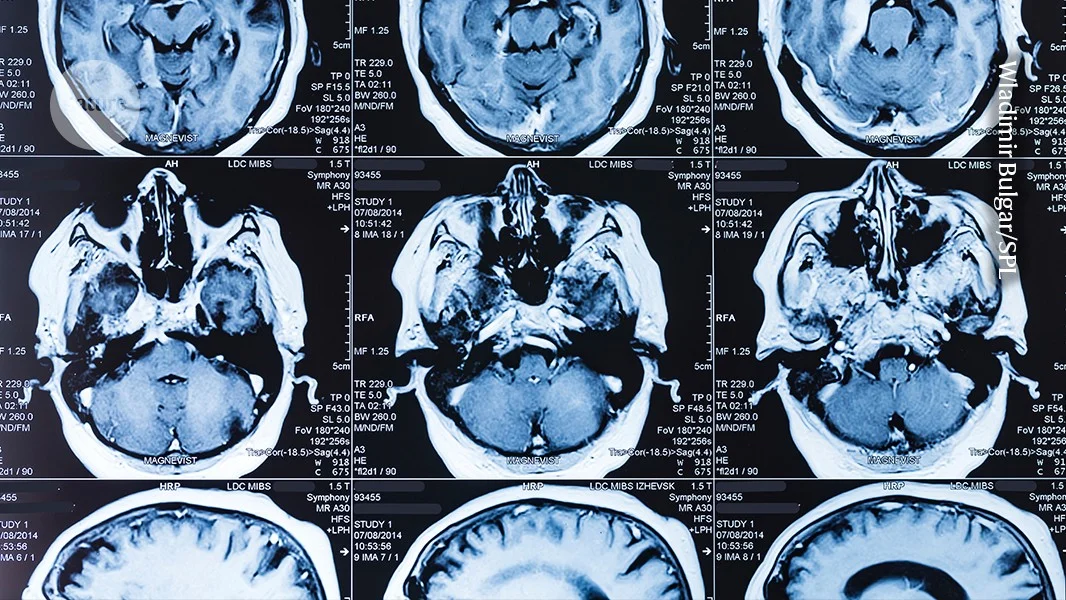

The article emphasizes the importance of protecting fundamental research, which often leads to groundbreaking discoveries like MRI and PCR tests, despite current financial pressures and misconceptions about its immediate impact. It argues that long-term, curiosity-driven science is crucial for societal progress and should be adequately funded by governments.